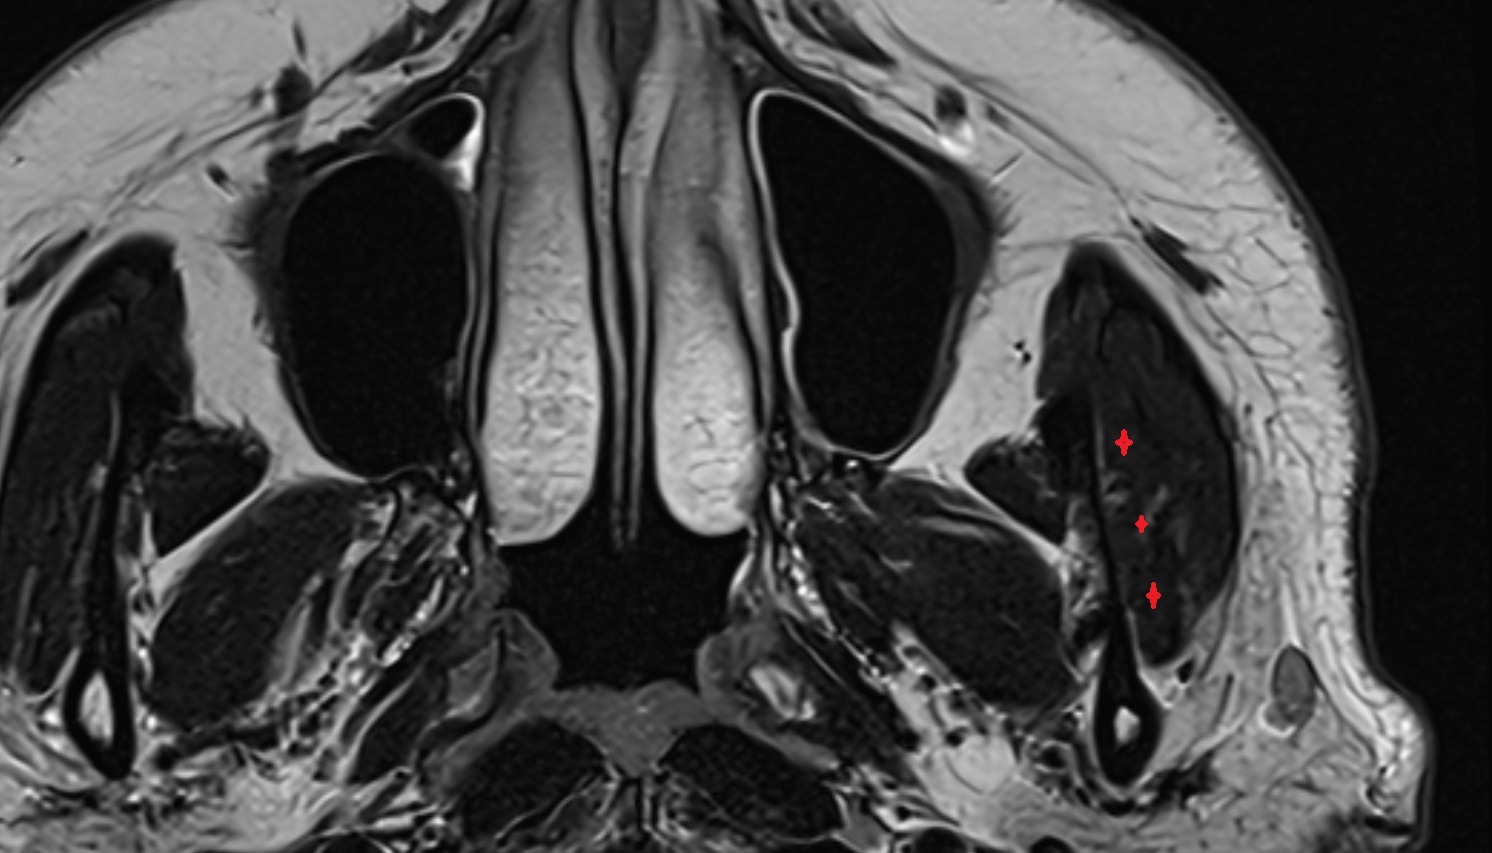

- Lateral rectus muscle

- Medial rectus muscle

- Orbital part of optic nerve

- Retrobulbar fat

- Inferior rectus muscle